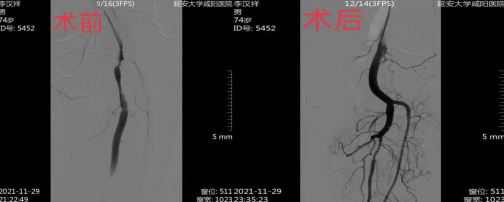

“醫(yī)生醫(yī)生,麻煩您了”“您一定要盡全力”“所有的字我都簽,錢不是問題”只見介入室門前一群家屬簇?fù)碇ぷ魅藛T,你一言我一語,“請(qǐng)您們放心,我們一定會(huì)盡最大的努力救治病人,這是我們的職責(zé),現(xiàn)在是爭(zhēng)分奪秒的時(shí)刻,治療越早效果越好,請(qǐng)您放心,安心等待,后面還需要照顧患者?!苯槿胧中g(shù)室內(nèi),只聽見患者因疼痛聲嘶力竭的叫喊聲和護(hù)士耐心細(xì)微地安慰聲:“深呼吸醫(yī)生正在給您處理,請(qǐng)您堅(jiān)持一下,疼的話握緊我的手......”經(jīng)過醫(yī)生精湛的操作技術(shù),護(hù)士全力以赴配合,最終造影顯示血管完美暢通。洗手衣早已完全浸濕,累的早已直不起了腰,看到患者完美地結(jié)局,懸著的心終于放下來了,這樣的場(chǎng)景在這里習(xí)以為常。